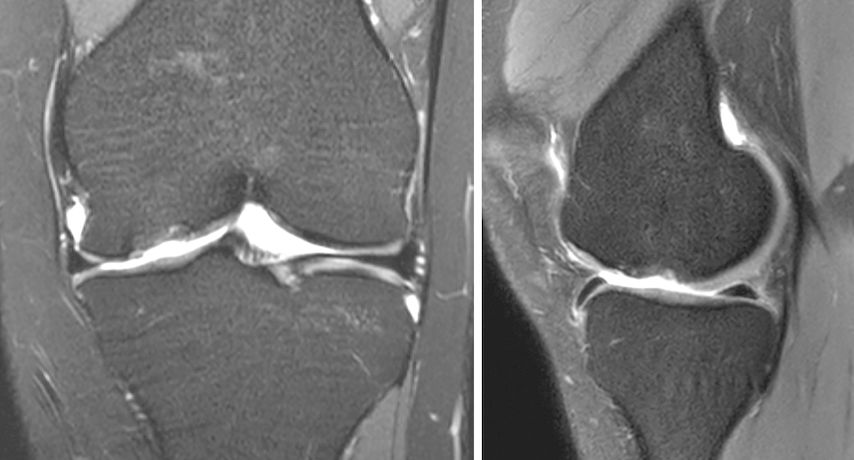

Abb. 1a und b: MRI-Bildgebung präoperativ bei grossem, vollflächigem Knorpelschaden an der medialen Femurkondyle einer jungen Patientin

Abb. 1f: MRI-Bildgebung 2 Jahre postoperativ nach Minced-Cartilage-Chirurgie bei Knorpeldefekt im Bereich der Trochlea femoris